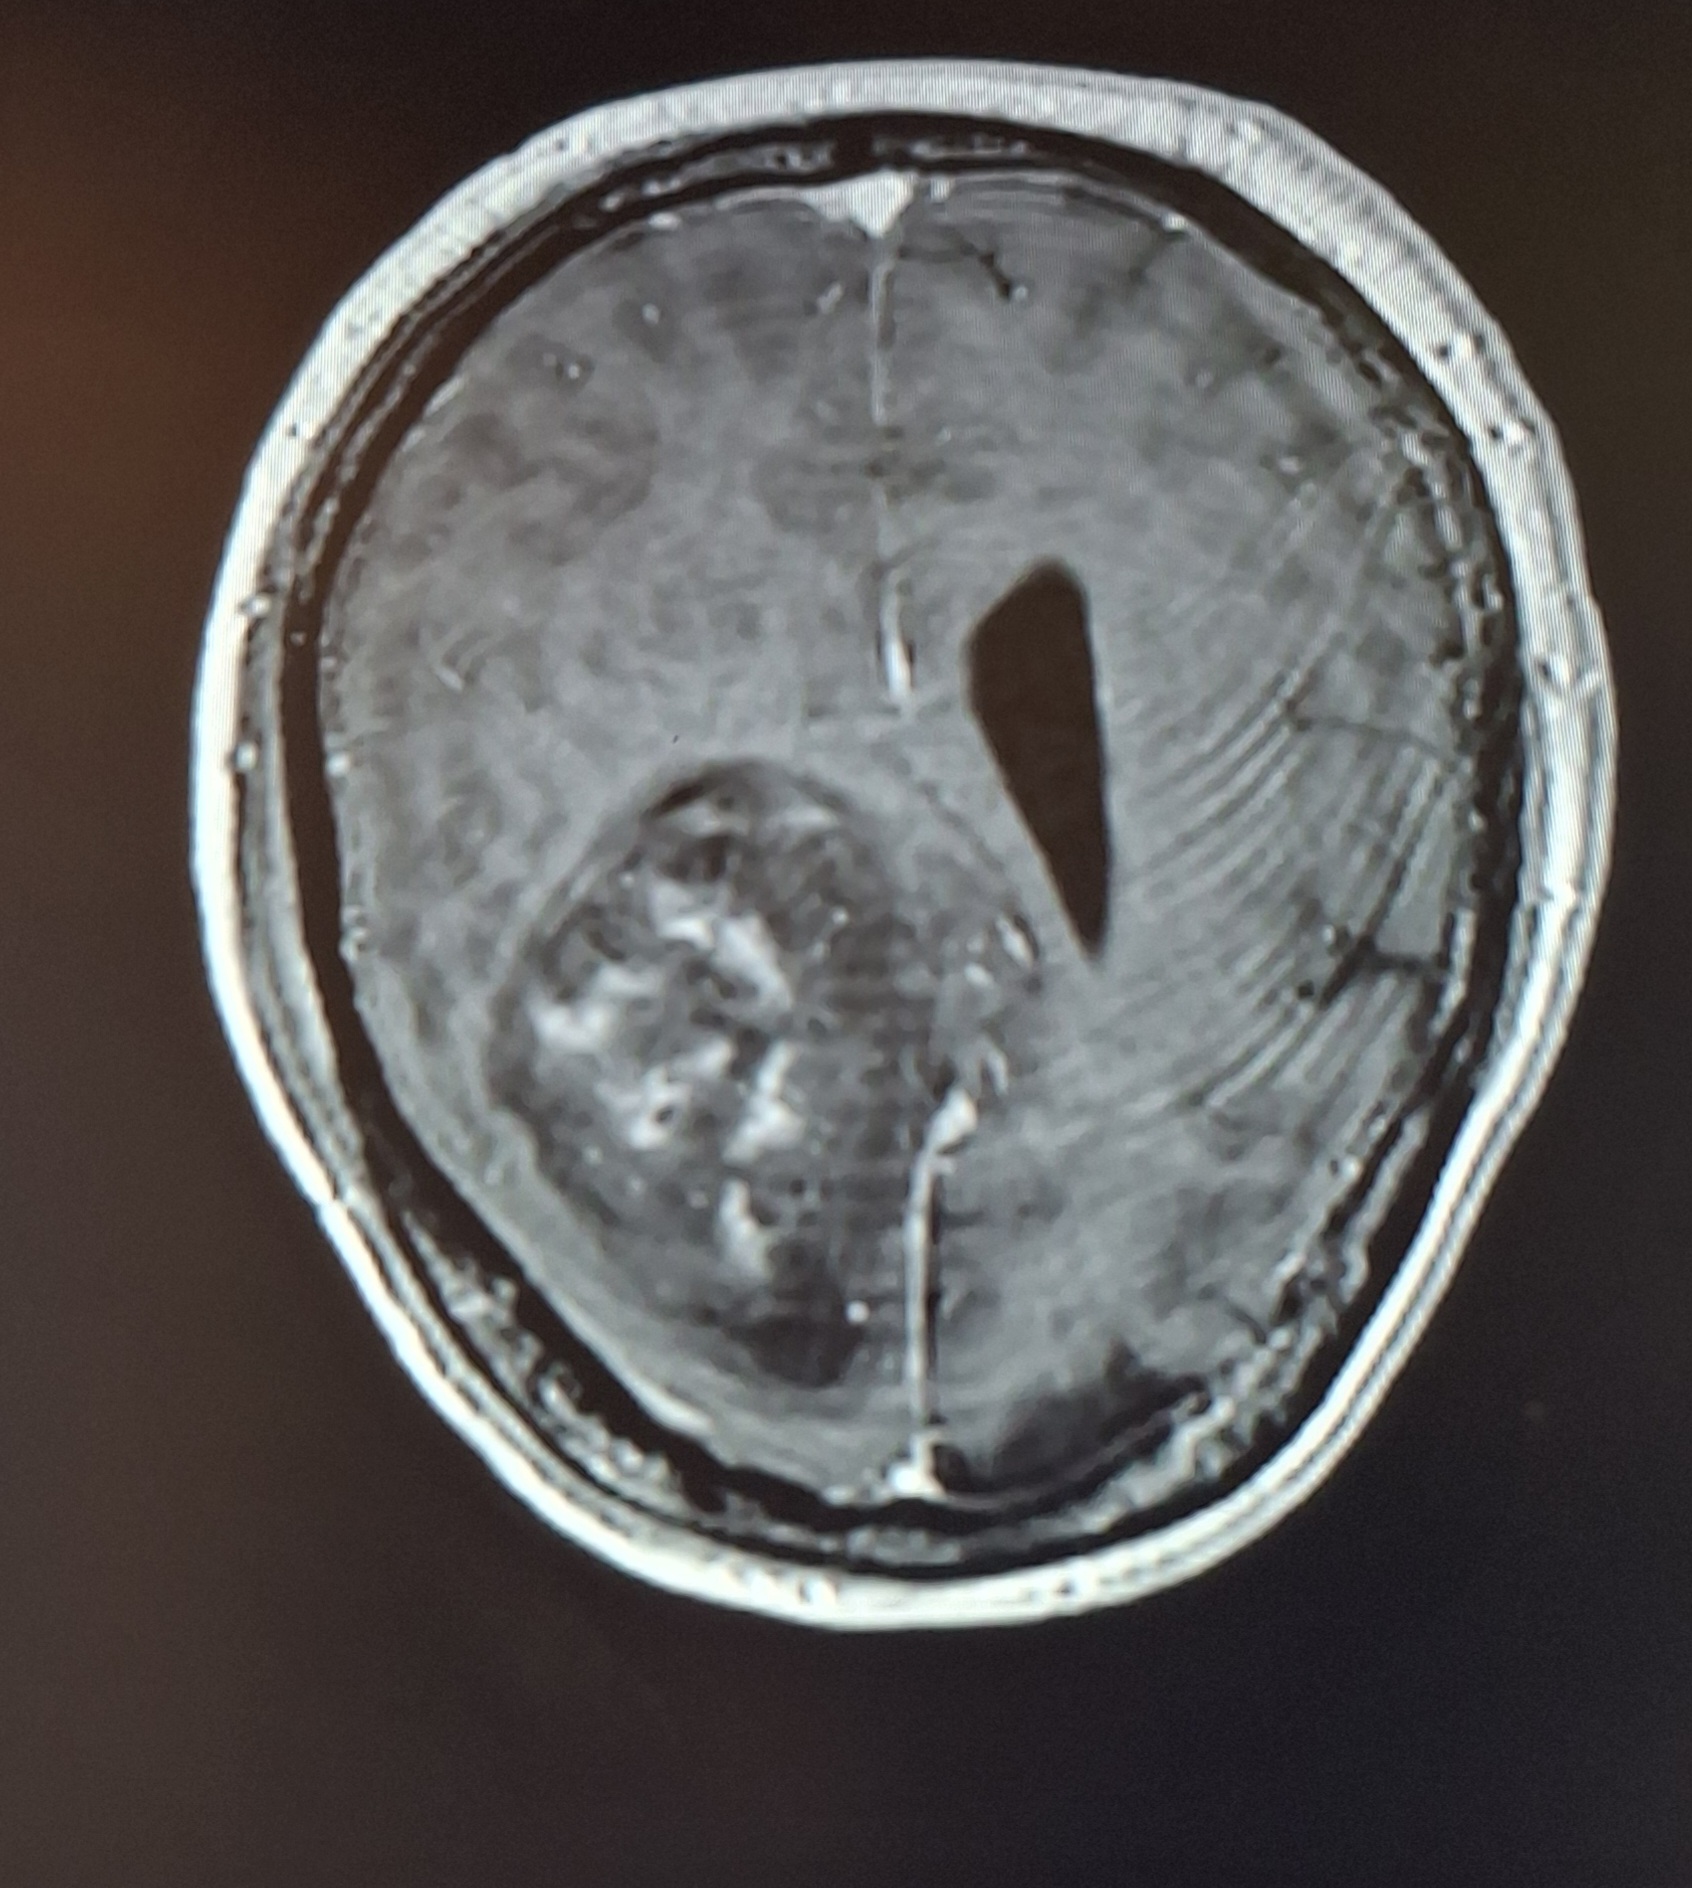

We were shown his scans for the first time, and the reality was overwhelming. The tumour was the size of a tennis ball — approximately 7.5 × 5 cm — a life threatening mass dominating the left side of his brain. We were warned that surgery carried significant risks, including permanent brain damage and even death.

On 23 April 2025, Alex underwent an emergency six hour craniotomy at the Royal Victoria Hospital. The tumour was in the left frontal lobe — the area that controls speech, mobility, personality, and so many of the things that make someone who they are.